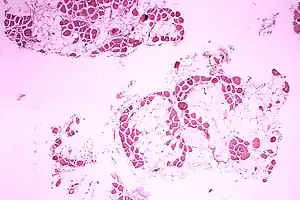

| Microscopic image of cross-sectional calf muscle from a person with Duchenne muscular dystrophy, showing extensive replacement of muscle fibers by fat cells. | |

DMD causes progressive muscle weakness due to muscle fiber disarray, death, and replacement with connective tissue or fat.[3] The voluntary muscles are affected first, especially those of the hips, pelvic area, thighs, calves.[9][10] It eventually progresses to the shoulders and neck, followed by arms, respiratory muscles, and other areas.[10] Fatigue is common.[11]

A classic sign of DMD is trouble getting up from lying or sitting position,[15] as manifested by a positive Gowers's sign. When a child tries to arise from lying on his stomach, he compensates for pelvic muscle weakness through use of the upper extremities:[13] first by rising to stand on his arms and knees, and then "walking" his hands up his legs to stand upright. Another characteristic sign of DMD is pseudohypertrophy (enlarging) of the muscles of the tongue, calves, buttocks, and shoulders (around age 4 or 5). The muscle tissue is eventually replaced by fat and connective tissue, hence the term pseudohypertrophy. Muscle fiber deformities and muscle contractures of Achilles tendon and hamstrings can occur, which impair functionality because the muscle fibers shorten and fibrose in connective tissue.[10] Skeletal deformities can occur, such as lumbar hyperlordosis, scoliosis, anterior pelvic tilt, and chest deformities. Lumbar hyperlordosis is thought to be compensatory mechanism in response to gluteal and quadriceps muscle weakness, all of which cause altered posture and gait (e.g.: restricted hip extension).[17][18]